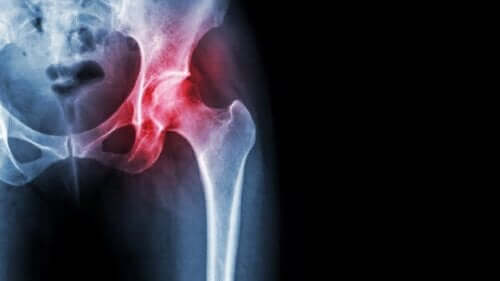

النخر اللاوعائي لرأس الفخذ

يحدث النخر اللاوعائي، مثله مثل جميع حالات النخر، بسبب نقص إمداد الأنسجة بالدم. في هذه الحالة بالذات يؤثر على العظام، مما يؤدي إلى عواقب وخيمة للغاية. في هذه المقالة، سنصف ما هو النخر اللاوعائي لرأس الفخذ وكيف يؤثر على جودة حياة المرضى وخيارات العلاج المتاحة لهم.